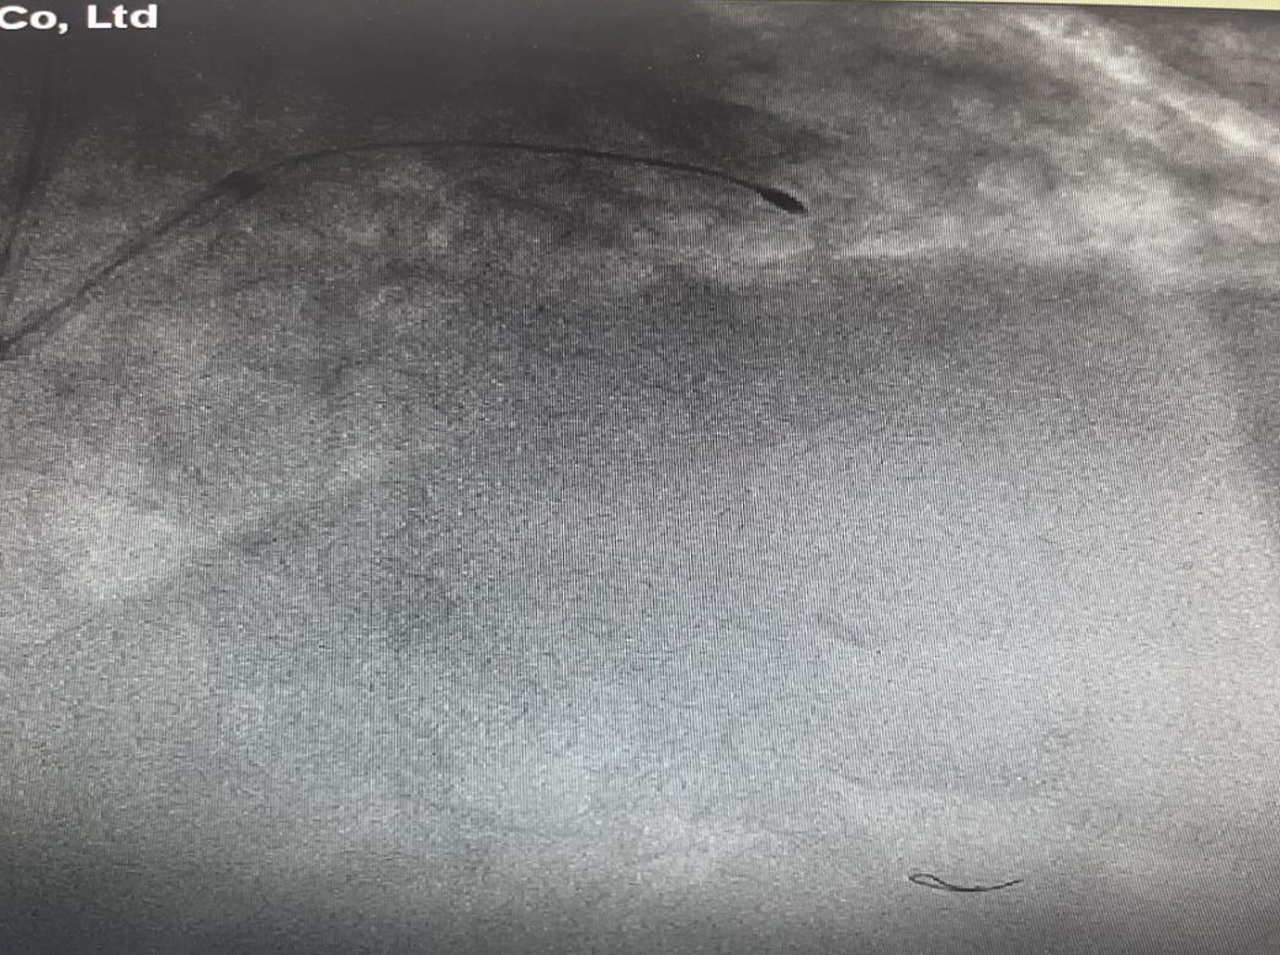

前降支病变处旋磨中

手术中